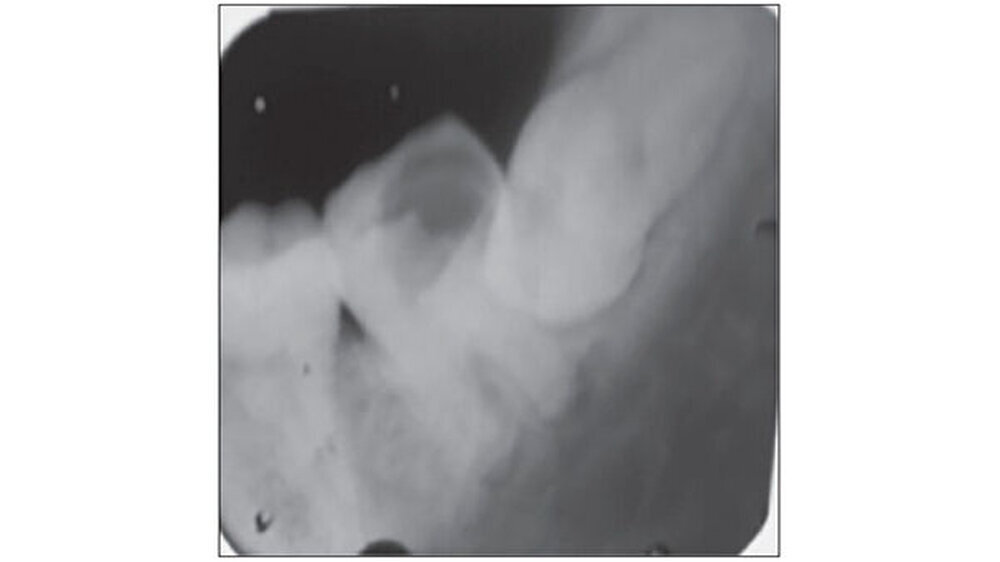

Eine 27-jährige Patientin stellte sich mit Schmerzen im linken Unterkiefer in der Abteilung für Zahnerhaltung und Endodontie am Himachal Dental College in Himachal Pradesh , Indien, vor. Die klinische und radiologische Untersuchung ergab, dass der Zahn 37 stark kariös war. Zudem lag eine chronische irreversible Pulpitis und apikale Parodontitis vor. Der Zahn 38 zeigte horizontale Einbrüche (Abbildung 1). Daher wurde beschlossen, 37 und 38 gleichzeitig zu extrahieren und den 38 in die Extraktionsstelle des 37 zu transplantieren.

Die Anästhesie erfolgte mit Lidocain-Hydrochlorid (Lignox zwei Prozent, Indoco-Remedies Ltd., India). Zuerst erfolgte die Extraktion von Zahn 37 extrahiert - ohne die Corticales zu beschädigen. Danach erst erfolgte die Extraktion von Zahn 38, um hier die Gewebeschäden so gering wie möglich zu halten. Eine horizontale intrakrevikuläre Inzision wurde durchgeführt. Zahn 38 wurde bis zur Transplantation in isotoner Kochsalzlösung gelagert, parallel eine Socket Preparation vorbereitet (Abbildung 2).